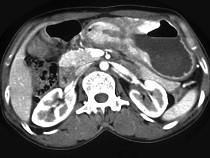

问题 女,56岁,上腹部钝痛、腹胀不适1月余,纳差、消瘦,影像检查如图,最可能的诊断是()

选项 A.胃幽门管溃疡 B.胃腺癌并幽门狭窄 C.胃淋巴瘤 D.胃间质瘤 E.胃恶性间质瘤

答案 B